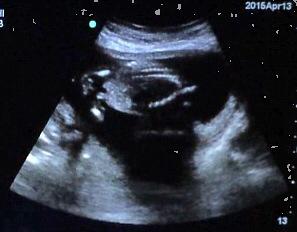

I had posted a few weeks ago that I went for a korean scan off post, it lasted 1:56 and the lady said she didnt she penis. Ok, well I had my 17 wk check up and Dr asked if I wanted to see baby. Of course!! Baby was moving like crazy and she couldn't get an actual potty shot but I have a few shots. So, I took video and these pictures are from the video.

My question, Do you see any gender clues? Skull??? Thank you for looking!!!

Profile Of Baby

Attachment 24766